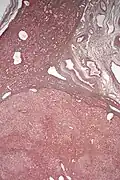

Inflammatory hepatocellular adenoma